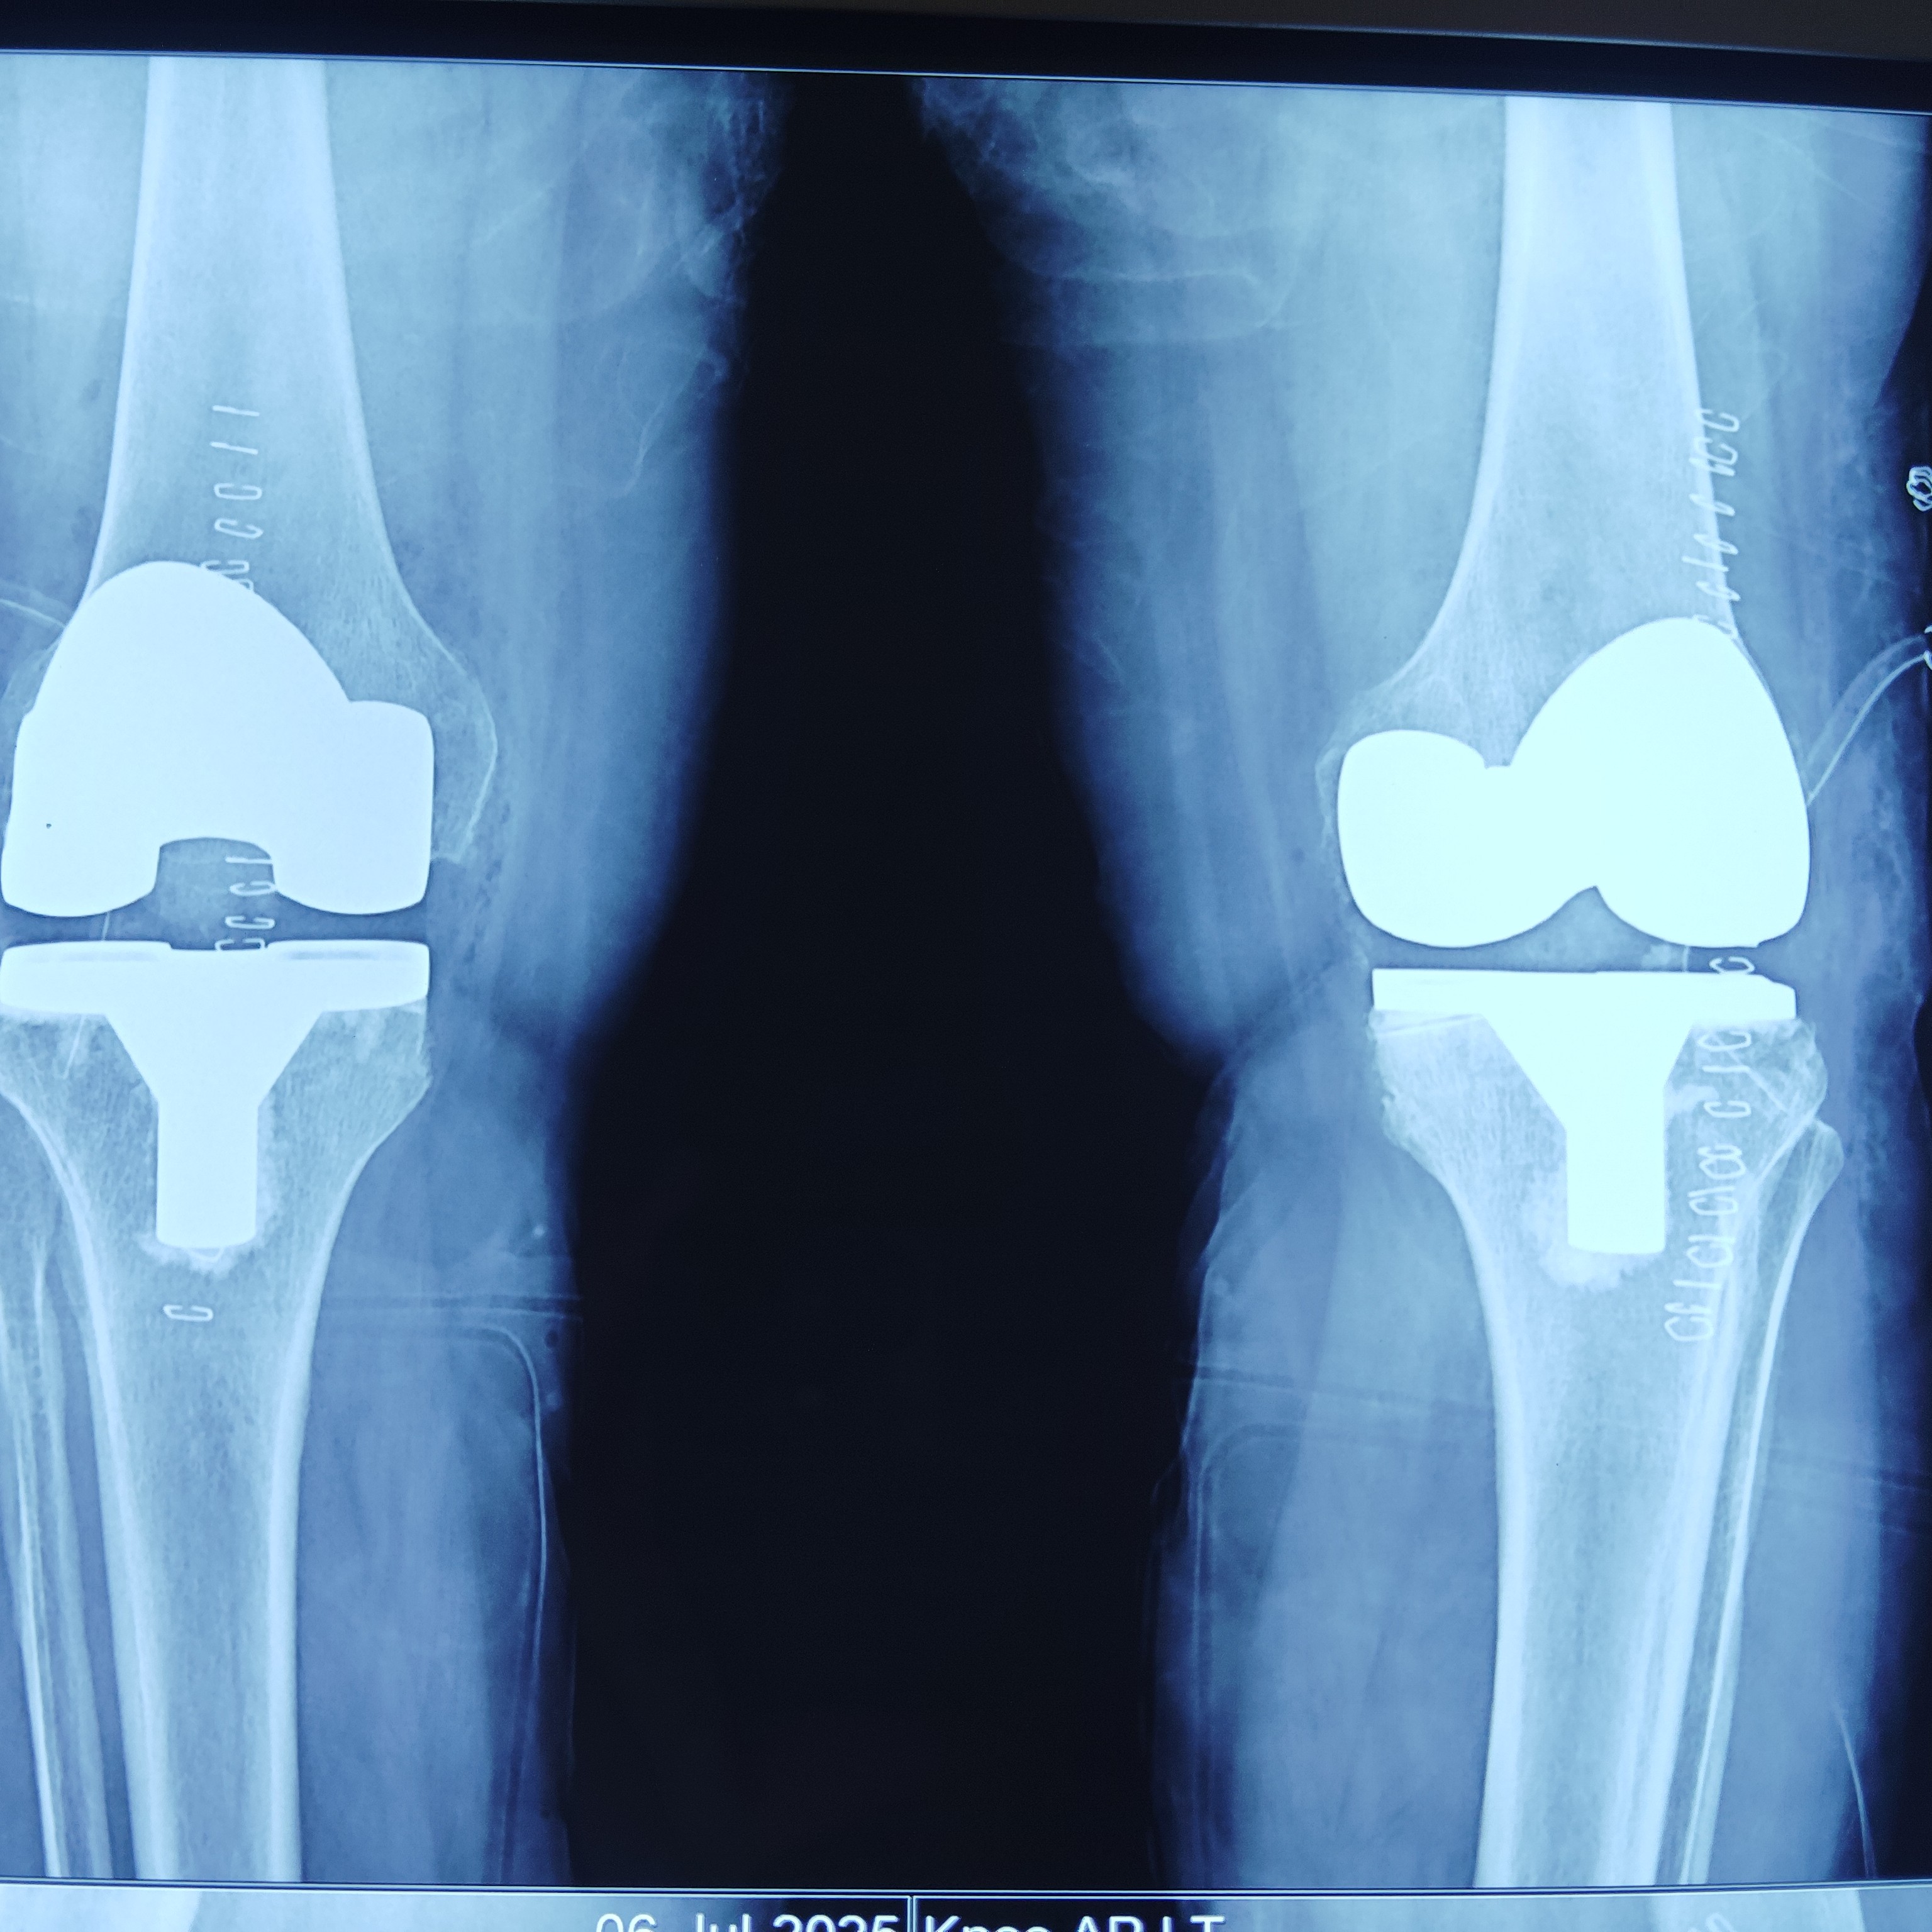

Successful KNEE REPLACEMENT surgery in Greater Noida